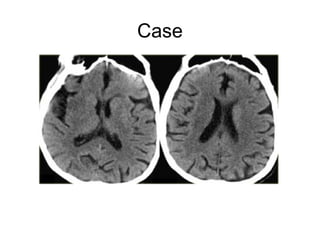

Case

CT Perfusion